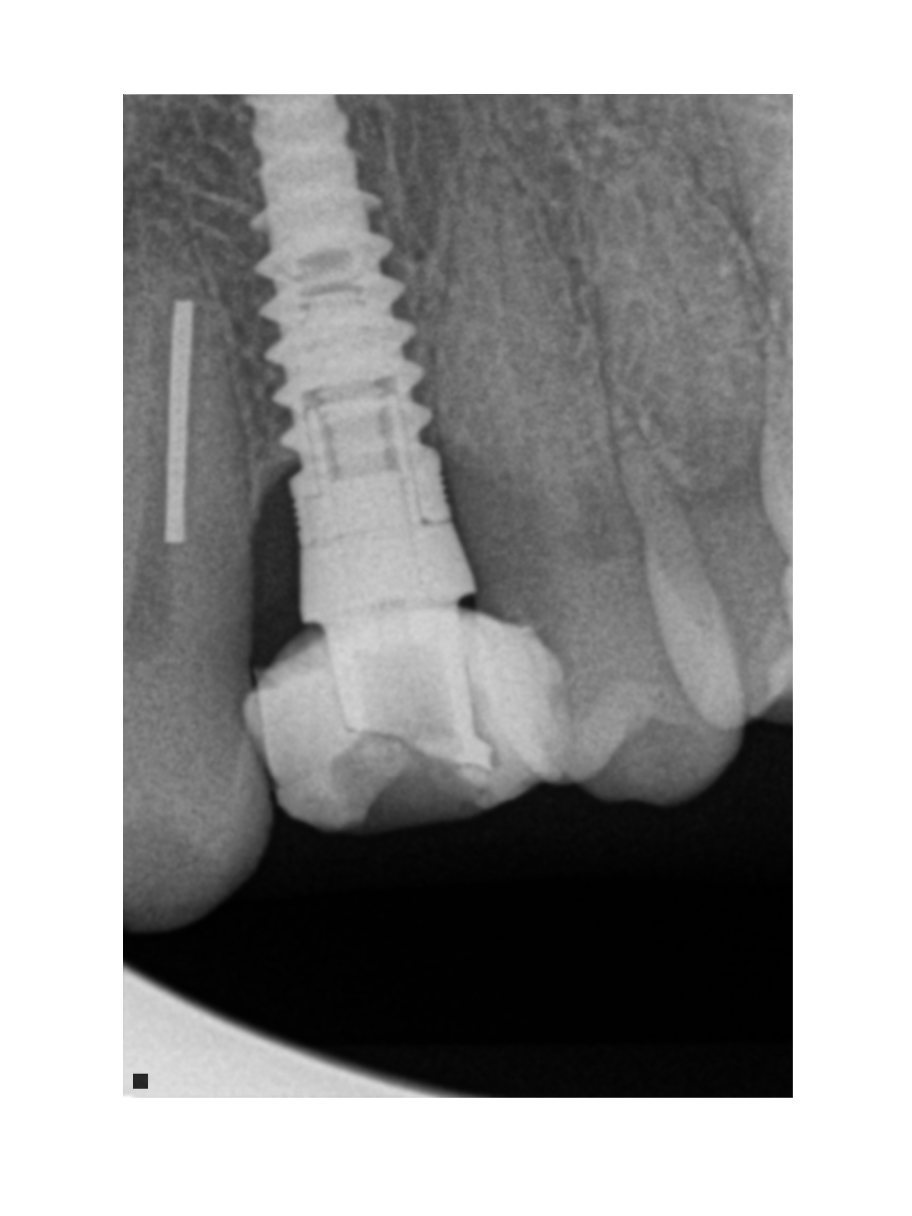

Implante 37 , qué tipo de implante es?

Paciente acude a consulta con corona sobre ioi con movilidad, retiramos corona y encontramos un pilar atornillado y en el interior de la corona otro pilar cementado a la corona [...]